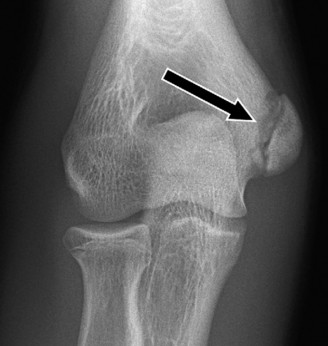

Understand common complications associated with performing surgery for scapulothoracic bursitis? CASE 33 A 42-year-old female presents to the office for follow up after sustaining a minimally displaced radial head fracture 3 months prior. She states she was initially treated in long-arm splint by the ER and did not follow up with an orthopaedic surgeon until now. Per her report, she removed the splint 4 weeks after the injury, but did not move her elbow due to pain. She now has no pain but is unable to reach that hand to her face or head. The remaining history is significant for previous ulnar nerve surgery for which she is unable to provide details. On physical examination, her upper extremity is normal except for limited flexion/extension, measured to be 80 to 50 degrees by goniometer. In addition, she has a well-healed surgical incision about the medial elbow, consistent with a previous surgery on her ulnar nerve. Her images are shown (Figs. 2–82 to 2–84).

Figure 2–82

Figure 2–83

Figure 2–84

The correct answer is (A). Classification of post-traumatic elbow stiffness allows for better understanding of the disease and allows the clinician to treat the underlying cause of the joint contracture. Intrinsic causes include: any problem within the joint such as incongruency, loose bodies, or severe osteoarthritis. Extrinsic causes include capsular tightness, muscle contracture, heterotopic ossification, and skin contractures. Early is defined as within 6 months of the injury while late is considered to be greater than 6 months after the injury. Patients that present in the early time frame have a significantly better chance at having a good result both from nonoperative and operative treatment.